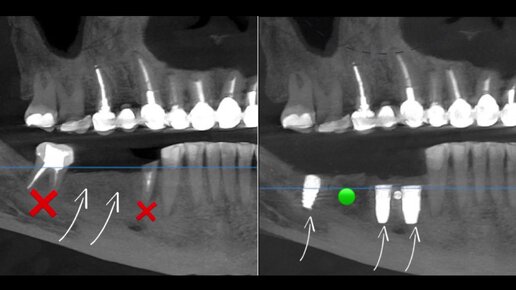

Имплантация зубов Nobel

Стоматологические клиники MAGIC DENT г. Сочи